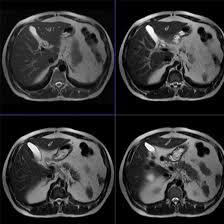

MRI Upper Abdomen With Contrast

Medifyhome has collaborated with the best pathology laboratories that are NABL and NABH certified and follow ISO safety guidelines to provide the best MRI Upper Abdomen With Contrast at an affordable price for needy individuals. Magnetic Resonance Imaging (MRI) of the upper abdomen with contrast is an advanced imaging technique that provides detailed views of the abdominal organs, including the liver, pancreas, kidneys, gallbladder, and spleen. This procedure enhances the visualization of soft tissues, allowing for more accurate diagnosis and assessment of various medical conditions. Using a gadolinium-based contrast agent, the MRI improves the differentiation between normal and abnormal tissues. This is particularly useful in identifying tumors, cysts, inflammation, and vascular abnormalities. The contrast agent highlights blood vessels and enhances the visibility of lesions, making it easier for healthcare providers to determine the nature and extent of any abnormalities.This non-invasive imaging technique is invaluable in various clinical scenarios, including the evaluation of liver diseases, pancreatic disorders, and urinary tract issues. Patients typically undergo this procedure after thorough preparation, which may include fasting and avoiding certain medications. By utilizing high-resolution imaging capabilities and advanced contrast techniques, MRI of the upper abdomen plays a crucial role in guiding treatment decisions and monitoring disease progression, ultimately contributing to improved patient care and outcomes.